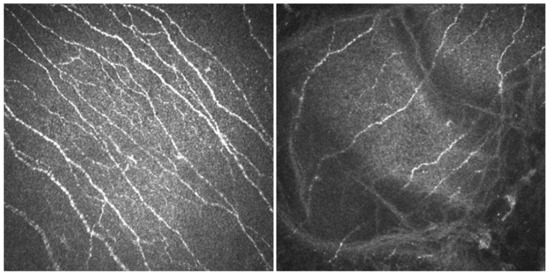

- In vivo confocal microscopy (IVCM). Laser scanning IVCM of the cornea was performed using the Rostock cornea module of the Heidelberg Retina Tomograph 3 (Heidelberg Engineering GmbH, Heidelberg, Germany). Before examination, a drop of anesthetic was instilled, and an eye speculum was used to keep the lids wide open. A drop of Viscotears Gel (Carbomer 980, 0.2%; Novartis Farmacéutica S.A., Barcelona, Spain) was deposited on the objective lens, thus avoiding direct contact of the TomoCap with the cornea. At least three good quality, non-overlapping images from the sub-basal nerve plexus of the central cornea were obtained using sequence and/or volume scans, and were used for the analysis. Each image was comprised of 384 × 384 pixels covering an area of 400 × 400 μM (0.16 mm2) with a transverse optical resolution of 2 μM, an axial optical resolution of 4 μM, and an acquisition time of 0.024 s.For IVCM image analysis, two masked observers analyzed the following in the three images: (1) nerve morphology parameters of density, length, branching density, and grade of tortuosity; (2) density of dendritic cells; (3) presence of neuromas; and (4) reflectivity from the confocal images, as an index of optic densitometry or transparency of cornea [14]. The mean value between the two observers for each parameter was computed for statistical analysis.Nerve density (n/mm2) and length (mm/mm2) were measured using the plugin NeuronJ (http://www.imagescience.org/meijering/software/neuronj/ accessed on 25 May 2021) from the ImageJ and provides quantification. The number of nerve branch points and dendritic cells (identified in the sub-basal nerve plexus by their distinctive features, i.e., bright cell bodies with dendritic form structures), were manually determined using the multipoint tool of the ImageJ software, and the densities calculated (n/mm2) as described in a previous study [15]. The grade of nerve tortuosity was evaluated according to the scale (0–4) reported by Oliveira-Soto and Efron [16] for main nerves. The histogram of each image based on the ImageJ plugin was used to obtain the mean reflectivity or optic densitometry [14]. These parameters were compared with well-established values for normal corneas and performed with the same type of confocal microscope. Specifically, we used data from Giannacare et al. [17] for nerve length, and from our group for nerve density, density of nerve branches, density of dendritic cells, [15] and nerve tortuosity and reflectivity [14].

3.3. IVCM Findings